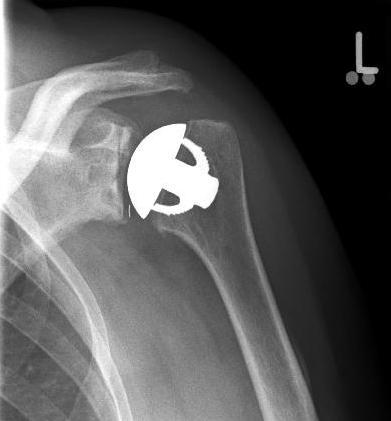

Surface replacement ("cap prosthesis" of the humeral head) in cases of mild omarthrosis and still well-preserved glenoid cavity

links: X-ray image of a cap prosthesis ("surface replacement")

right: cap prosthesis ("surface replacement", type "Durom" Fa. Zimmer)gkl